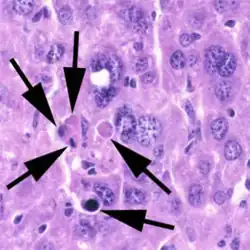

Kenmerken van apoptose

Een cel die apoptose ondergaat is te herkennen aan een aantal kenmerken. Het duidelijkste morfologische kenmerk is het afsplitsen van kleine bolletjes cytoplasma met celinhoud (blebbing). Ook kunnen apoptotische cellen worden herkend aan DNA fragmentatie als gevolg van afbraak van het DNA. Cellen die apoptose ondergaan vertonen ook negatief geladen fosfolipiden op het celoppervlak. Deze negatief geladen fosfolipiden kunnen door fagocyten herkend worden. Na herkenning verwijdert de fagocyt de apoptotische cel.